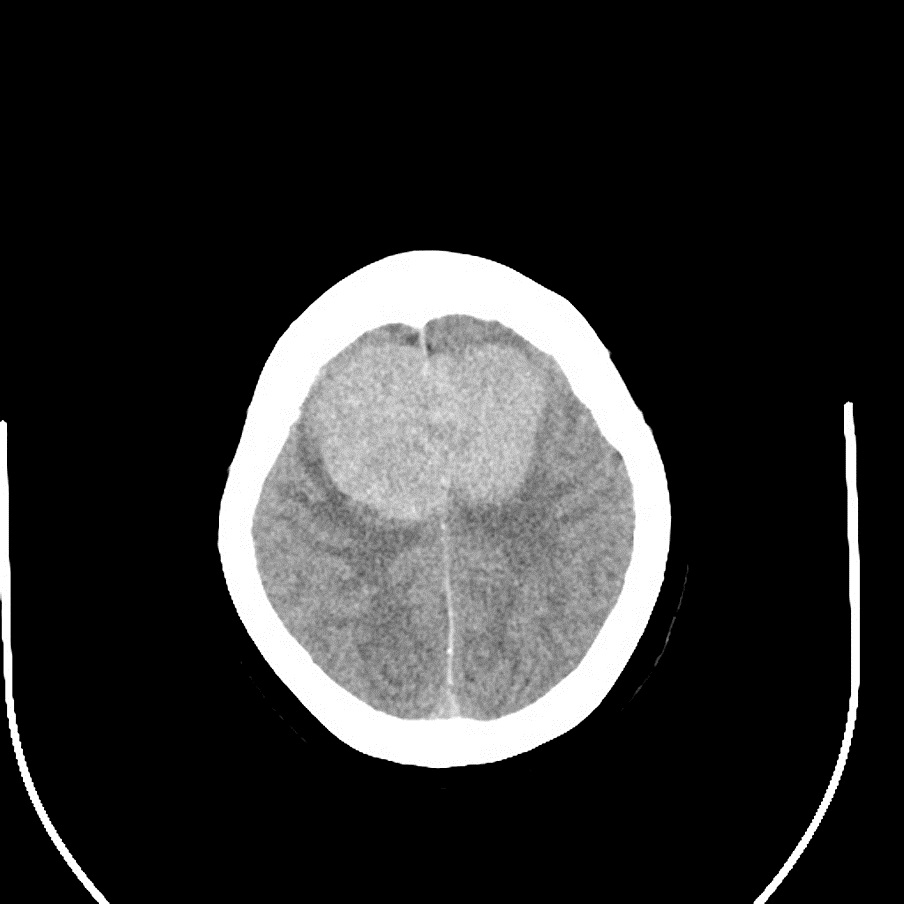

2016年8月,54岁的李某因“双侧大脑镰矢状窦旁巨大脑膜瘤”(直径达6.5厘米)四处求医,诊断明确;却因居住深山区,家庭贫困,支付不起昂贵的医疗费用想要放弃治疗。几经周折,李某最后来到嵩县人民医院神经外科就诊。神经外科医务人员经过全面评估,认为李某具备手术条件。

手术历时13小时(如上图),肿瘤全部被切除,且患者术后无明显的后遗症,得到省市级医院专家的一致认可。这也是嵩县人民医院神经外科具有里程碑意义的一台手术,充分显示了该科的技术实力,取得了较大的社会影响。

手术前